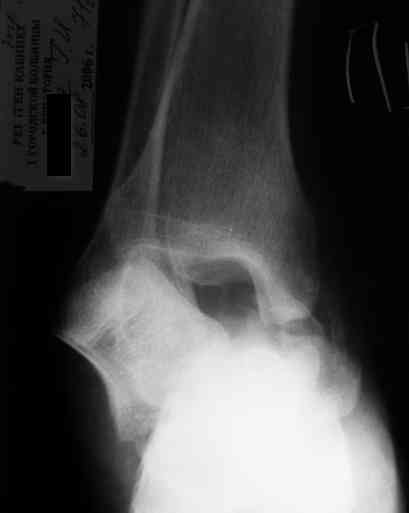

Уважаемый Александр! Как обещал представляю Р-граммы и операционные фото.

Ваши (лично ваши) рекомендации - астрагалэктомия-аппаратный пяточно-большеберцовый артродез с одновременным удлинением голени - правильно?

Можно убрать таранную кость, и поместить в образовавшуюся полость либо бусы из цемента с антибиотиками, либо вылепленный прямо по форме тарана спейсер. Целесообразность этого будет определяться распространенностью гнойного процесса. Может быть, будет достаточно только удаления тарана.

Вместе с аваскулярным куском кости устранится субстрат. Надо опасаться не мягких тканей, а плохо кровоснабжаемых. Если после удаления тарана добиться контакта хорошо васкуляризованных пятки и больщшеберцовой, мягкие ткани не давить, чтобы некроза раны не было, то все должно зажить.

Стабильность дает возможность расти сосудам. При хорошем кровоснабжении смежных фрагментов это все, что надо. А здесь есть большой секвестр. Разумно ли ждать, пока он васкуляризуется? Очевидно, без некрэктомии проблему не решить.